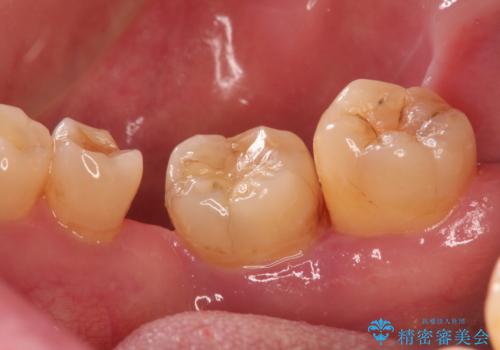

大きなむし歯と欠損をセラミックに 部分矯正を併用した総合歯科治療